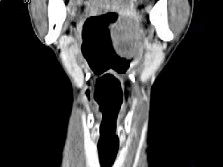

男,67岁,口咽部异物感约8个月,伴口咽部疼痛,患者无明显发热。如图所示最可能的诊断为()

男,67岁,口咽部异物感约8个月,伴口咽部疼痛,患者无明显发热,影像检查如图,最可能的诊断是<img border="0" style="width: 294px;

[单选题]男,67岁,口咽部异物感约8个月,伴口咽部疼痛,患者无明显发热,影像检查如图,最可能的诊断是A.扁桃体结核伴淋巴结转移B.扁桃体脓肿伴淋巴结转移C.扁

男,67岁,口咽部异物感约8个月,伴口咽部疼痛,患者无明显发热,影像检查如图,最可能的诊断是<img border="0" style="width: 297px;

[单选题]男,67岁,口咽部异物感约8个月,伴口咽部疼痛,患者无明显发热,影像检查如图,最可能的诊断是A.扁桃体结核伴淋巴结转移B.扁桃体脓肿伴淋巴结转移C.扁

男,67岁,口咽部异物感约8个月,伴口咽部疼痛,患者无明显发热,影像检查如图,最可能的诊断是()<img border="0" style="width: 224p

[单选题]男,67岁,口咽部异物感约8个月,伴口咽部疼痛,患者无明显发热,影像检查如图,最可能的诊断是()A.扁桃体结核伴淋巴结转移B.扁桃体脓肿伴淋巴结转移C

男,67岁,口咽部异物感约8个月,伴口咽部疼痛,患者无明显发热,影像检查如图,最可能的诊断是( )。<br /><img border="0" style=&q

[单选题]男,67岁,口咽部异物感约8个月,伴口咽部疼痛,患者无明显发热,影像检查如图,最可能的诊断是( )。A.扁桃体结核伴淋巴结转移B.扁桃体脓肿伴淋巴结

男,67岁,口咽部异物感约8个月,伴口咽部疼痛,患者无明显发热。如图所示最可能的

[单选题,A1型题] 男,67岁,口咽部异物感约8个月,伴口咽部疼痛,患者无明显发热。如图所示最可能的诊断为()A . 扁桃体结核伴淋巴结转移B . 扁桃体脓肿伴淋巴结转移C . 扁桃体癌伴淋巴结转移D . 扁桃体淋巴瘤E . 下咽癌伴淋巴结转移

男,67岁,口咽部异物感约8个月,伴口咽部疼痛,患者无明显发热.如图所示最可能的

[单选题]男,67岁,口咽部异物感约8个月,伴口咽部疼痛,患者无明显发热.如图所示最可能的诊断为()A .扁桃体结核伴淋巴结转移B .扁桃体脓肿伴淋巴结转移C .扁桃体癌伴淋巴结转移D .扁桃体淋巴瘤E .下咽癌伴淋巴结转移

男,67岁,口咽部异物感约8个月,伴口咽部疼痛,患者无明显发热。最可能的诊断为(

[单选题]男,67岁,口咽部异物感约8个月,伴口咽部疼痛,患者无明显发热。最可能的诊断为()A . 扁桃体结核伴淋巴结转移B . 扁桃体脓肿伴淋巴结转移C . 扁桃体癌伴淋巴结转移D . 扁桃体淋巴瘤E . 下咽癌伴淋巴结转移

男,67岁,口咽部异物感约8个月,伴口咽部疼痛,患者无明显发热,影像检查如图,最

[单选题]男,67岁,口咽部异物感约8个月,伴口咽部疼痛,患者无明显发热,影像检查如图,最可能的诊断是()A . 扁桃体结核伴淋巴结转移B . 扁桃体脓肿伴淋巴结转移C . 扁桃体癌伴淋巴结转移D . 扁桃体淋巴瘤E . 下咽癌伴淋巴结转移